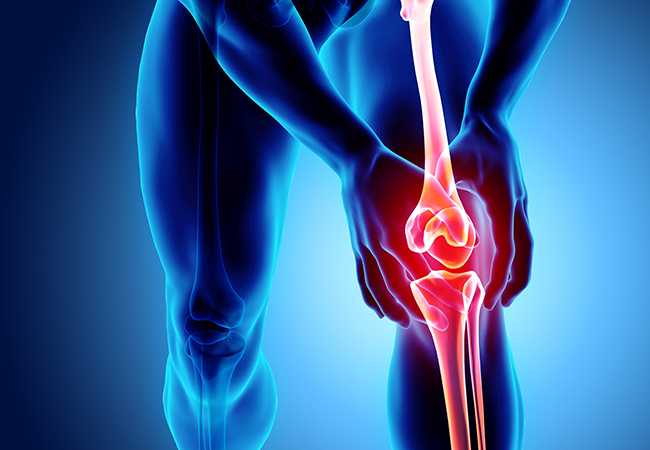

- Knee Pain

- ACL Injuries

- Arthritis Pain Relief

- Sports Injuries